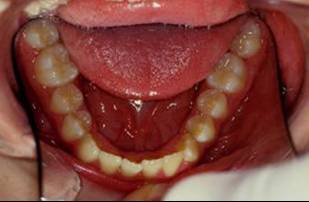

Collage bas fait presque 3 mois apres le haut, avec des elastiques verticaux pendant 3 semaines seulement. Et voici les photos, la suite je vous en passe car il s'agit de simple finition.

En realite les choses etaint deja dans le bon sens des le RDV du collage mandibulaire, si vous regarder les photos 13 et 14, la beance etait deja presque fermee, les elastiques etaient pour eviter que cela ne recidive. Donc le but n'etait pas d'egresser les dents pour fermer la beance mais plutot empecher les deux arcs de s'eloigner.

Comme je l'ai dit, je les ai utilise pendant 3 semaines seulement au moment du collage du bas, apres rien. Les dernieres photos sont presque 3 mois apres le collage du bas et l'arret des elastiques et la beance n'a pas recidive.